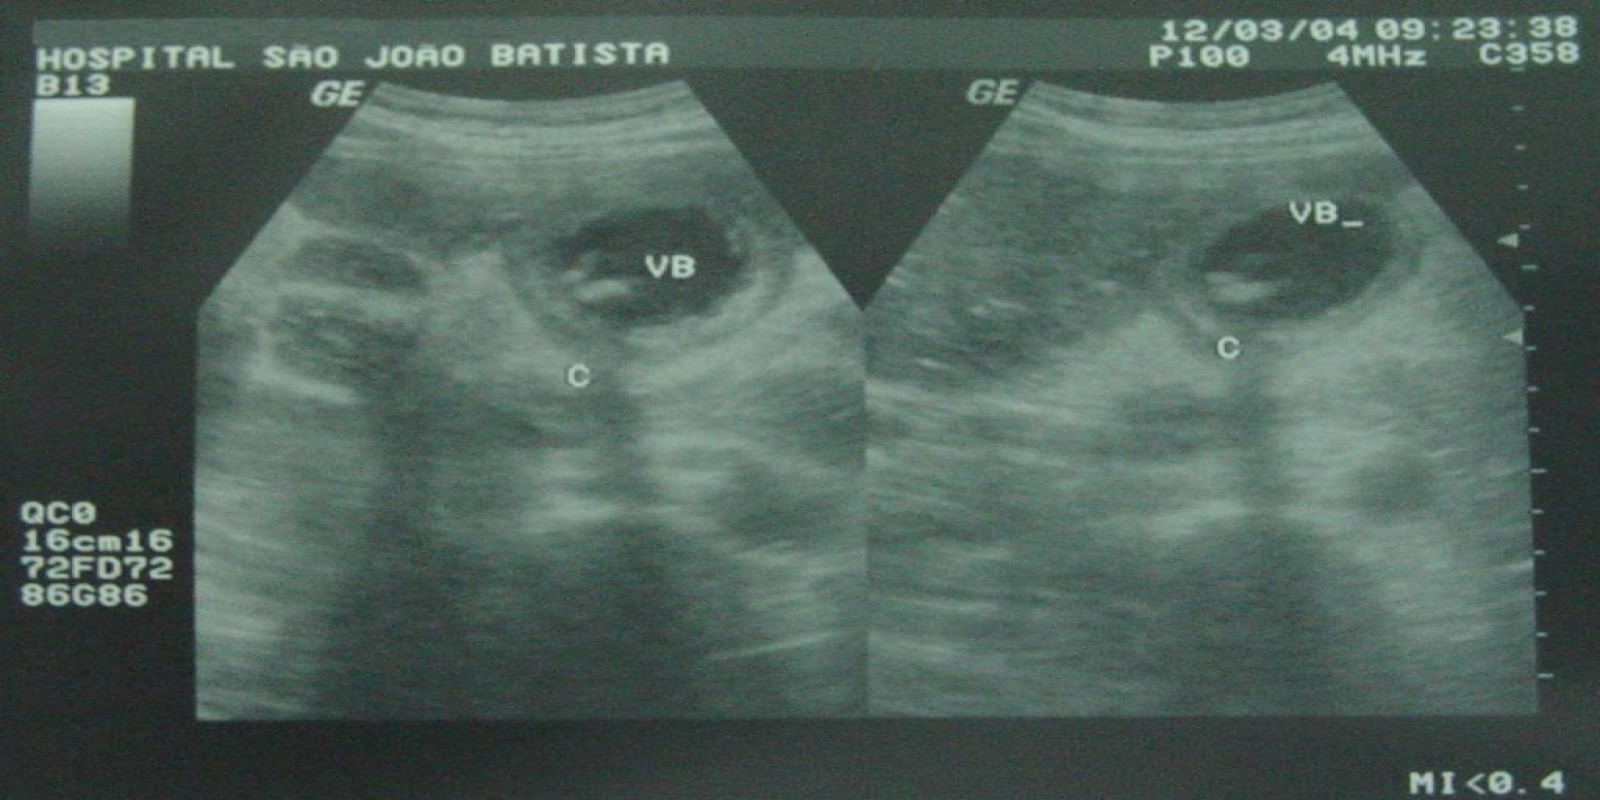

Colecistite Aguda

Acute Cholecystitis